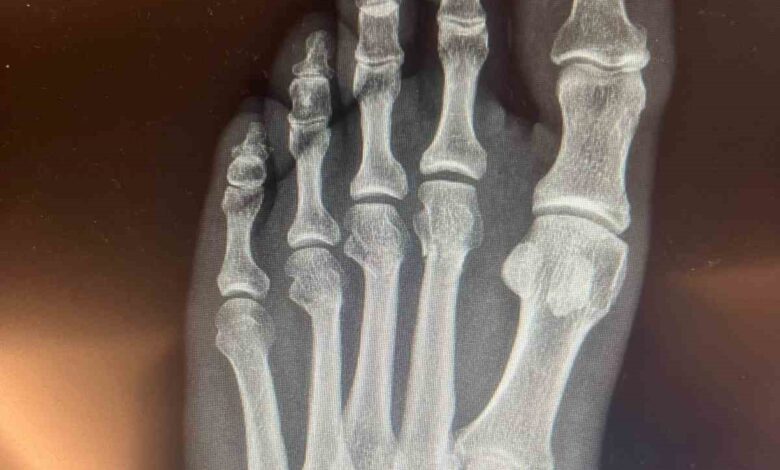

Özgür Özel ‘ayağından vuruldu’ iddialarına ilişkin kırılan ayağının röntgen filmlerini paylaştı

Cumhuriyet Halk Partisi (CHP) Genel Başkanı Özgür Özel, sosyal medyada yer alan ‘ayağından vuruldu’ iddialarına ilişkin, kırılan ayağının röntgen filmlerini paylaştı.

CHP Grup Başkanvekili Ali Mahir Başarır, geçen hafta TBMM’deki özel oturum öncesi gazetecilere yaptığı açıklamada, CHP Genel Başkanı Özgür Özel’in evde geçirdiği kaza sonucu ayağında ufak çaplı kırılma olduğunu duyurmuştu. Özel’in ayağında oluşan kırık hakkında sosyal medyada, Özel’in ‘ayağından vurulduğu’ iddiaları yer almıştı. Özel, tartışmalara ilişkin ayağının röntgen filmlerini paylaştı.